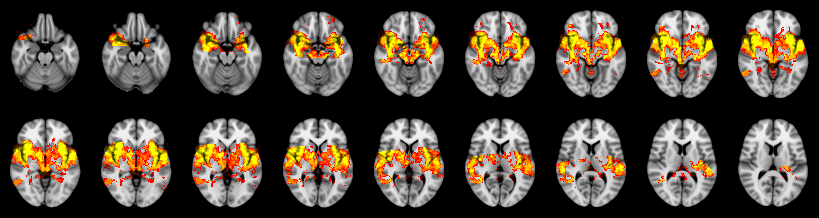

Pain study, TFCE, Uncorrected

Not combined

Face:

Hand:

Foot: